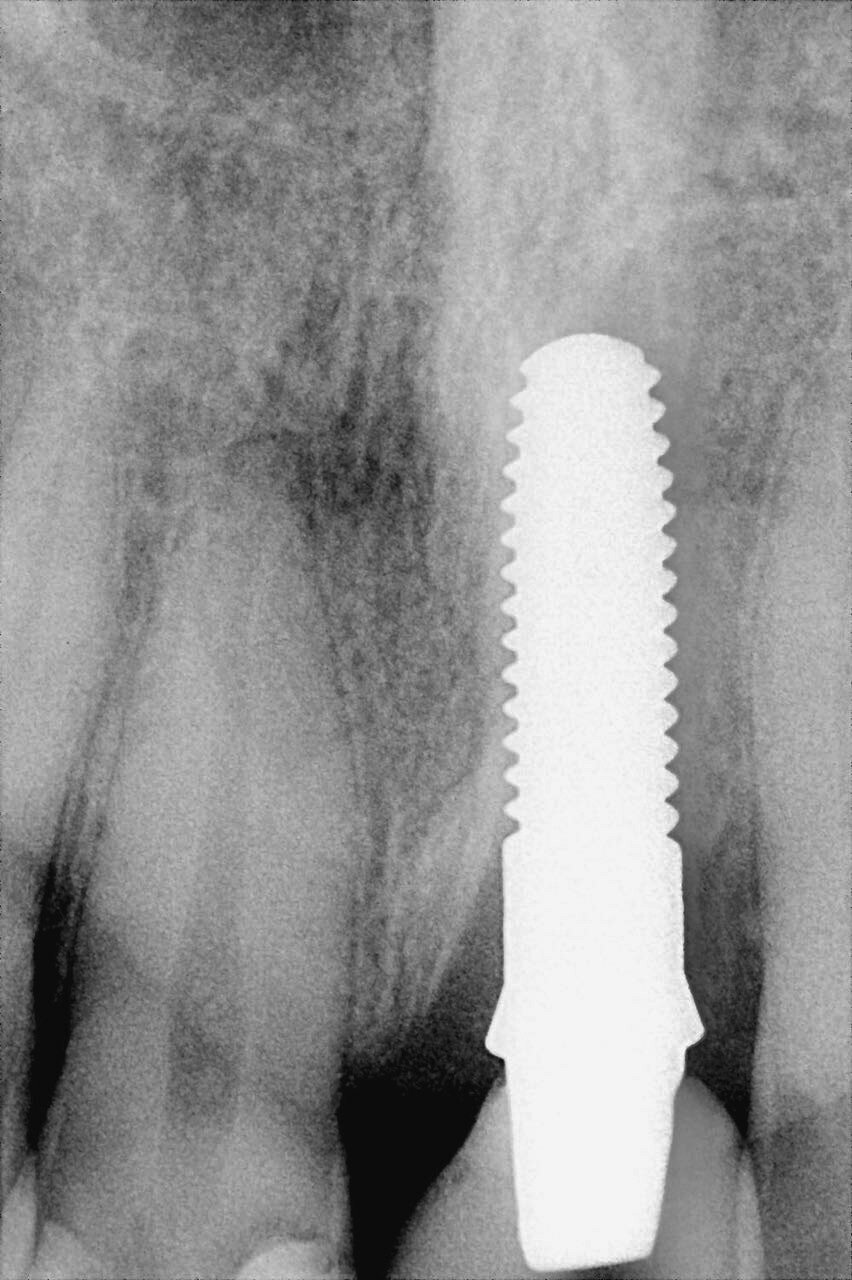

Situation postopératoire et radiographie après un an.

L’examen postopératoire un an plus tard n’a montré aucun signe de mobilité, de perte osseuse, de lacération des tissus péri-implantaires ou de paresthésie, pas plus qu’il n’y avait de signe d’inflammation du tissu mou (péri-implantaire) autour du site (Fig. 6).